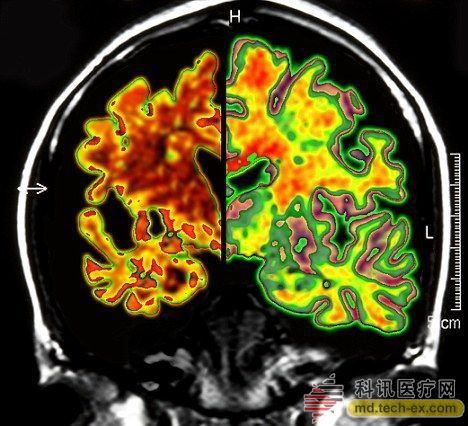

在手術(shù)中,所有病患的腦部將被植入電極,這些電極與一個(gè)類似起搏器的裝置相連接,能夠每秒鐘發(fā)出130次電脈沖。羅森博格表示,病人并不會感受到電脈沖的存在。 研究人員表示,所有接受臨床試驗(yàn)的病人同時(shí)都會被植入這個(gè)“起搏器”裝置。其中,一半病人的“起搏器”將于手術(shù)后兩周開啟,而另一半病人的要在手術(shù)后一年才會開啟。目前,參加臨床試驗(yàn)的病人和醫(yī)生并不知道分組情況。 其實(shí)早在2010年,加拿大就已經(jīng)對這種大腦“起搏器”展開臨床試驗(yàn)。當(dāng)時(shí),有6名輕微老年癡呆癥患者參加。當(dāng)時(shí)的試驗(yàn)結(jié)果顯示,在13個(gè)月的觀察期中,這些病患的葡糖糖代謝速度持續(xù)上升,這也就說明他們的大腦神經(jīng)元正在工作。而在同時(shí)期內(nèi),大部分老年癡呆癥患者的葡萄糖代謝水平則是在不斷下降。